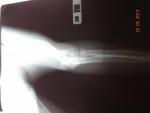

Увидев собаку, доктор Ягников сразу обратил внимание на неправильную походку и становление задних лап и предложил сделать рентген не только передних лап ( что впрочем мы уже подспудно ожидали ). Через 30 минут мы услышали диагноз. Он стал для нас шоком.

ПЕРЕДНИЙ локтевой сустав- локтевой отросток с трудночитаемым названием ( не пишем, боясь ошибиться в правильности написания -уточнить можно в скане диагноза в приложении к этому письму) требующий удаления.

Но это еще не самое страшное. ДИСПЛАЗИЯ ОБЕИХ задних лап, причем в очень серьезной стадии, одна из них практически на грани вывиха. ( в приложении- снимки рентген).

Итог озвученный доктором Ягниковым- «это ГЕНЕТИЧЕСКИЙ БРАК, собаку нужно вернуть заводчику, т.к. вам продали нездорового щенка. Дисплазия не лечится. В противном случае ( если вы захотите оставить щенка) вас в ближайшей перспективе ждут операции на трех лапах ( и может быть на задних придется делать повторные с вживлением металла в сустав) и долгое восстановление, антибиотики, таблетки и т.д. Нагрузки будут запрещены. Ни о каких выставках речи не идет. О размножении ( кабель же!) можно также забыть». Мы в шоке!!!! Слезы, нервные дни-вечера…Кто знает- тот поймет..

В течении месяца мы не могли принять решение. Прочитали кучу литературы на эту тему… И поехали к другому врачу. В этот раз к еще одному известному доктору- Еремину Д.А. ( хирург высшей квалификации, травматолог, ортопед, стаж 20 лет). Реакция один в один- только увидел щенка, сказал- тут проблема в задних лапах. Потом посмотрел снимки. ГЕНЕТИЧЕСКИЙ БРАК. Честно сказал: «я могу на вас заработать, ведь здесь будут операции и ни одна, потом трудное восстановление (постоянные антибиотики и таблетки что плохо повлияет на пищеварение, а у нас оно и так никуда не годное) т.к. собака вырастет 50-60 кг- это не шутки. С такой массой и такими лапами предсказать что-то невозможно. Но я бы собаку вернул. Понимаю жалко, но это будет правильно. На наш вопрос что будет через 10 лет- «о каких 10 лет идет речь, после операций и на таблетках- максимум 7».

Чуда как и ожидалось не произошло. Ситуация только ухудшилась. Что видно из снимков ( в приложении ). Дисплазия не исчезла, что и следовало ожидать.